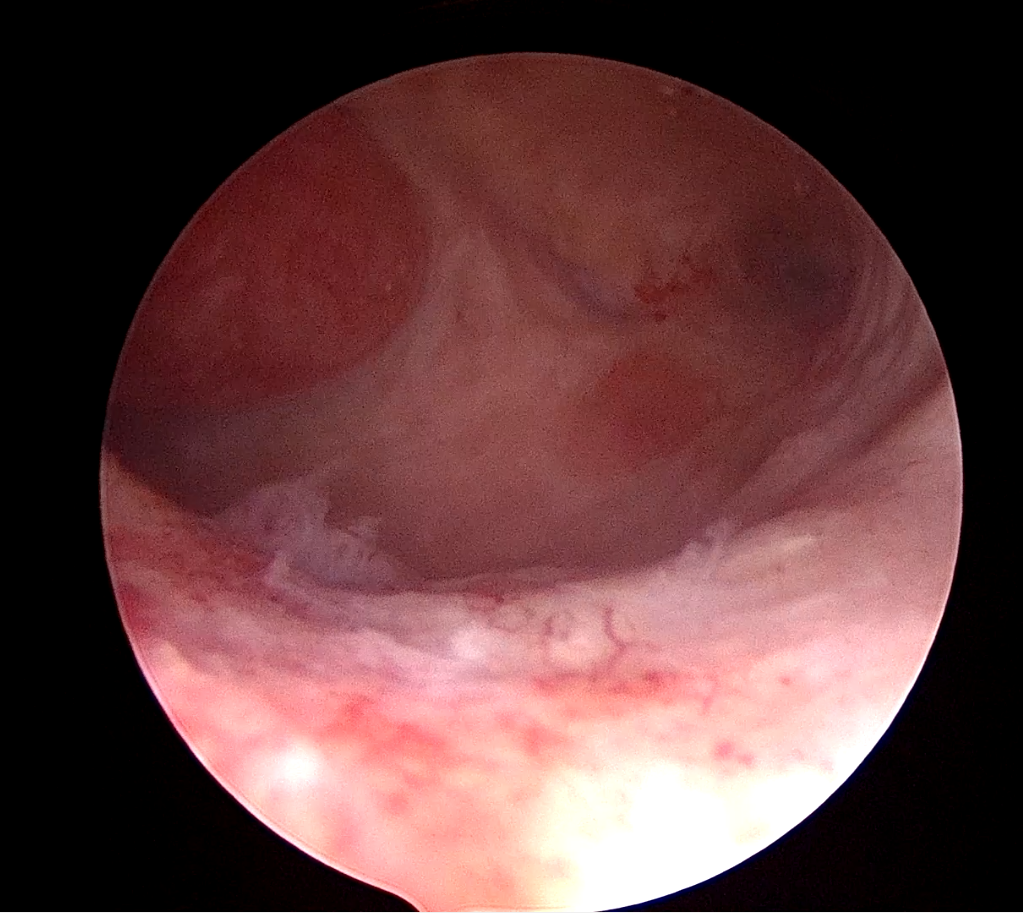

La biopsy snake grasper sec. VITALE (pinza a serpente sec. VITALE) è progettata per consentire prelievi endometriali mirati sotto visione diretta, permettendo di combinare in un unico gesto la presa, la trazione e la resezione del tessuto.

Grazie a queste caratteristiche è possibile ottenere campioni bioptici più ampi e di migliore qualità, adeguati all’analisi istologica anche in presenza di endometri ipotrofici o atrofici, con minore discomfort per la paziente e superando i limiti delle tecniche bioptiche “blind”.

L’introduzione della biopsy snake grasper sec. VITALE ha anche consentito lo sviluppo di una nuova tecnica di biopsia isteroscopica, la “pick-up biopsy”, che permette un campionamento mirato dell’endometrio mediante un aggancio selettivo e una trazione controllata del tessuto.

La pick-up biopsy si è dimostrata particolarmente efficace: